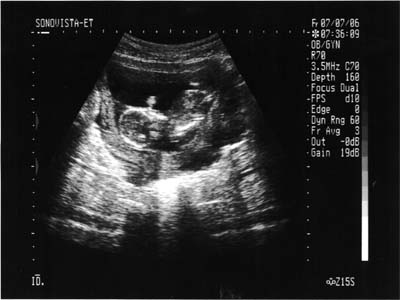

| 2006年7月7日(金) |

| 13w5d 4ヶ月検診を兼ねた助産師外来 寝てるようであまり動いてくれなくて心配したけど、 上げてた手(1枚目)を下に下げて(2枚目)動いてくれました。 助産師さんだったからか、大きさは測ってくれなかったのでわかりません。 |